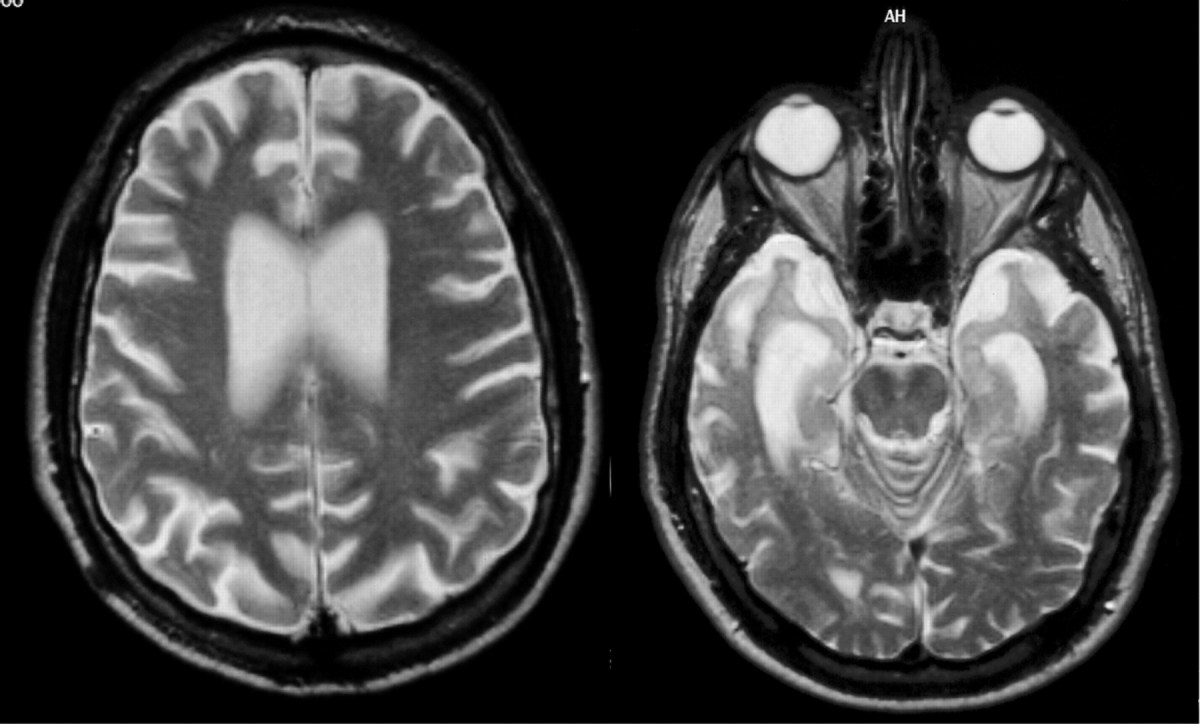

The Glymphatic system is largely active during sleep, although some activity can be found during wakeful hours. During sleep, the extracellular space in between brain cells is increased and flooded with Cerebrospinal Fluid (CSF) that collects waste metabolites & toxins. The waste fluid is then transported out of the brain, through the brain stem and spinal cord, until ultimately diffused into the bodies normal waste systems. It can be likened to a Car Wash for your brain.

Indeed, one study had researchers observe the flow of CSF in participants whilst breathing using MRI. They observed that CSF flowed almost exclusively with respiration. Forced breathing (Deep Breathing) elicited the highest flow of CSF whilst holding the breath suppressed the flow of CSF. (R)